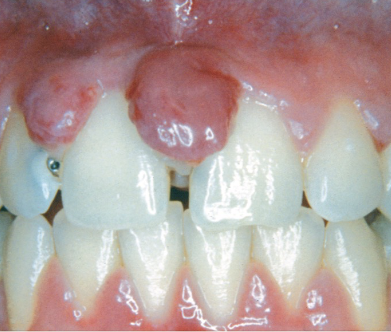

Describe tissue contour in gingivitis

Edema causes enlargement of gingival tissues

EX: Bulbous papilla